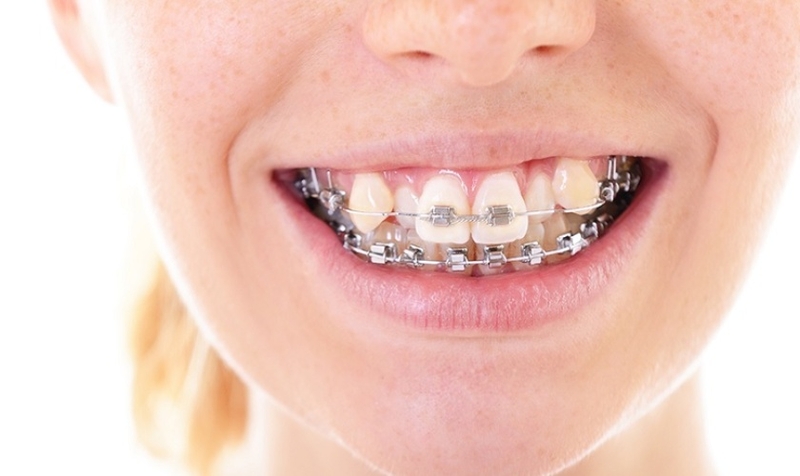

Niềng răng là một kỹ thuật điều trị răng bị mọc lệch, răng khểnh, hô răng, móm răng, răng mọc thưa, khớp cắn ngược,... Phương pháp niềng sẽ tác động và có hiệu quả dần theo thời gian bằng cách dùng các khí cụ để chỉnh răng, xương ổ răng nhằm đưa răng về vị trí chuẩn theo khớp cắn.

Bên cạnh đó, một số ít trường hợp sẽ cần nhổ răng để đạt hiệu quả chỉnh nha tối đa. Khi được gắn mắc cài/ khay niềng khách hàng sẽ được hẹn tái khám định kỳ để kiểm tra tình trạng dịch chuyển răng, siết dây cung hay điều trị một số vấn đề mắc phải ở răng trong suốt quá trình thực hiện niềng. Thời điểm cuối, khi tháo mắc cài nha sĩ sẽ tư vấn về việc đeo hàm duy trì để răng cố định hơn nhằm hoàn thiện quá trình chỉnh nha.

Niềng răng hiện được nhiều người ưa thích và lựa chọn bởi sự an toàn, ít xâm lấn, hiệu quả lâu dài cho răng. Thông thường răng khấp khểnh khi được chỉ định niềng sẽ gồm các giai đoạn với các tác dụng khác nhau: